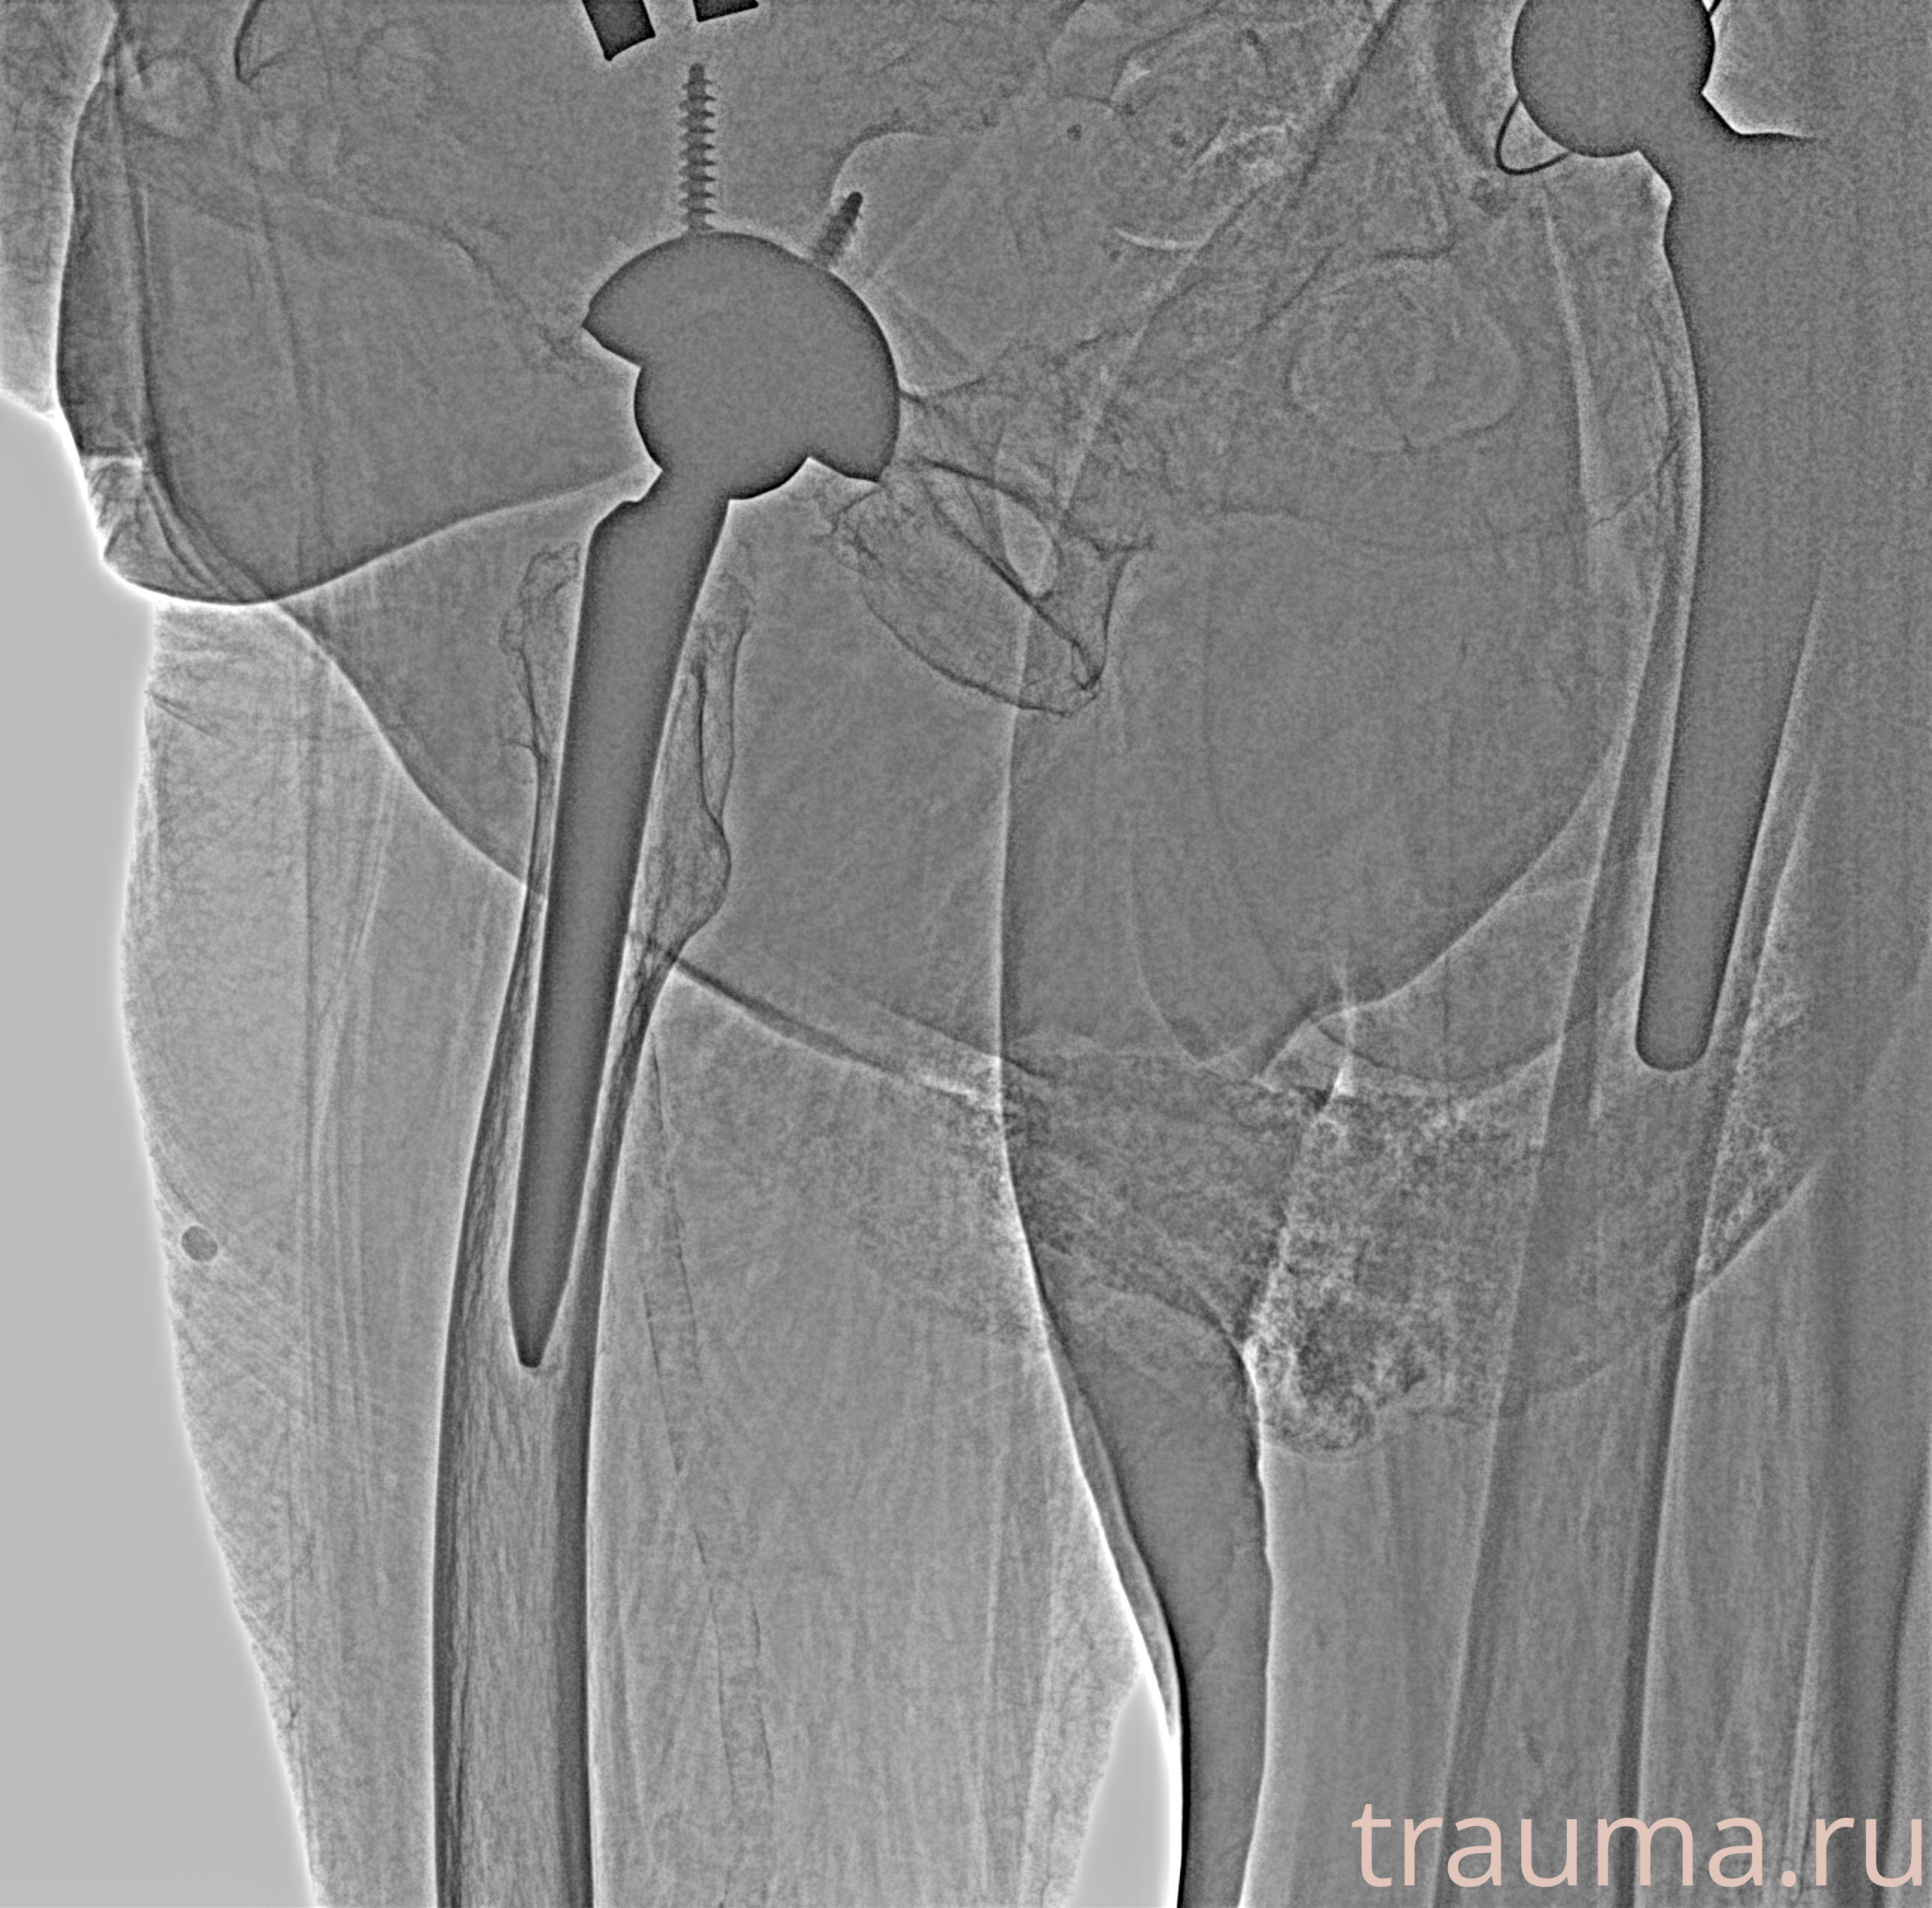

Рентгенограммы